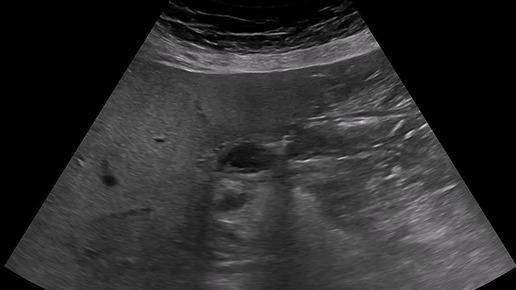

Ультразвуковые находки от врача УЗД Зорина Я.П.

Видео к статье "А ведь как похоже..." https://dzen.ru/a/aT_LeSB3aHHkpEj4